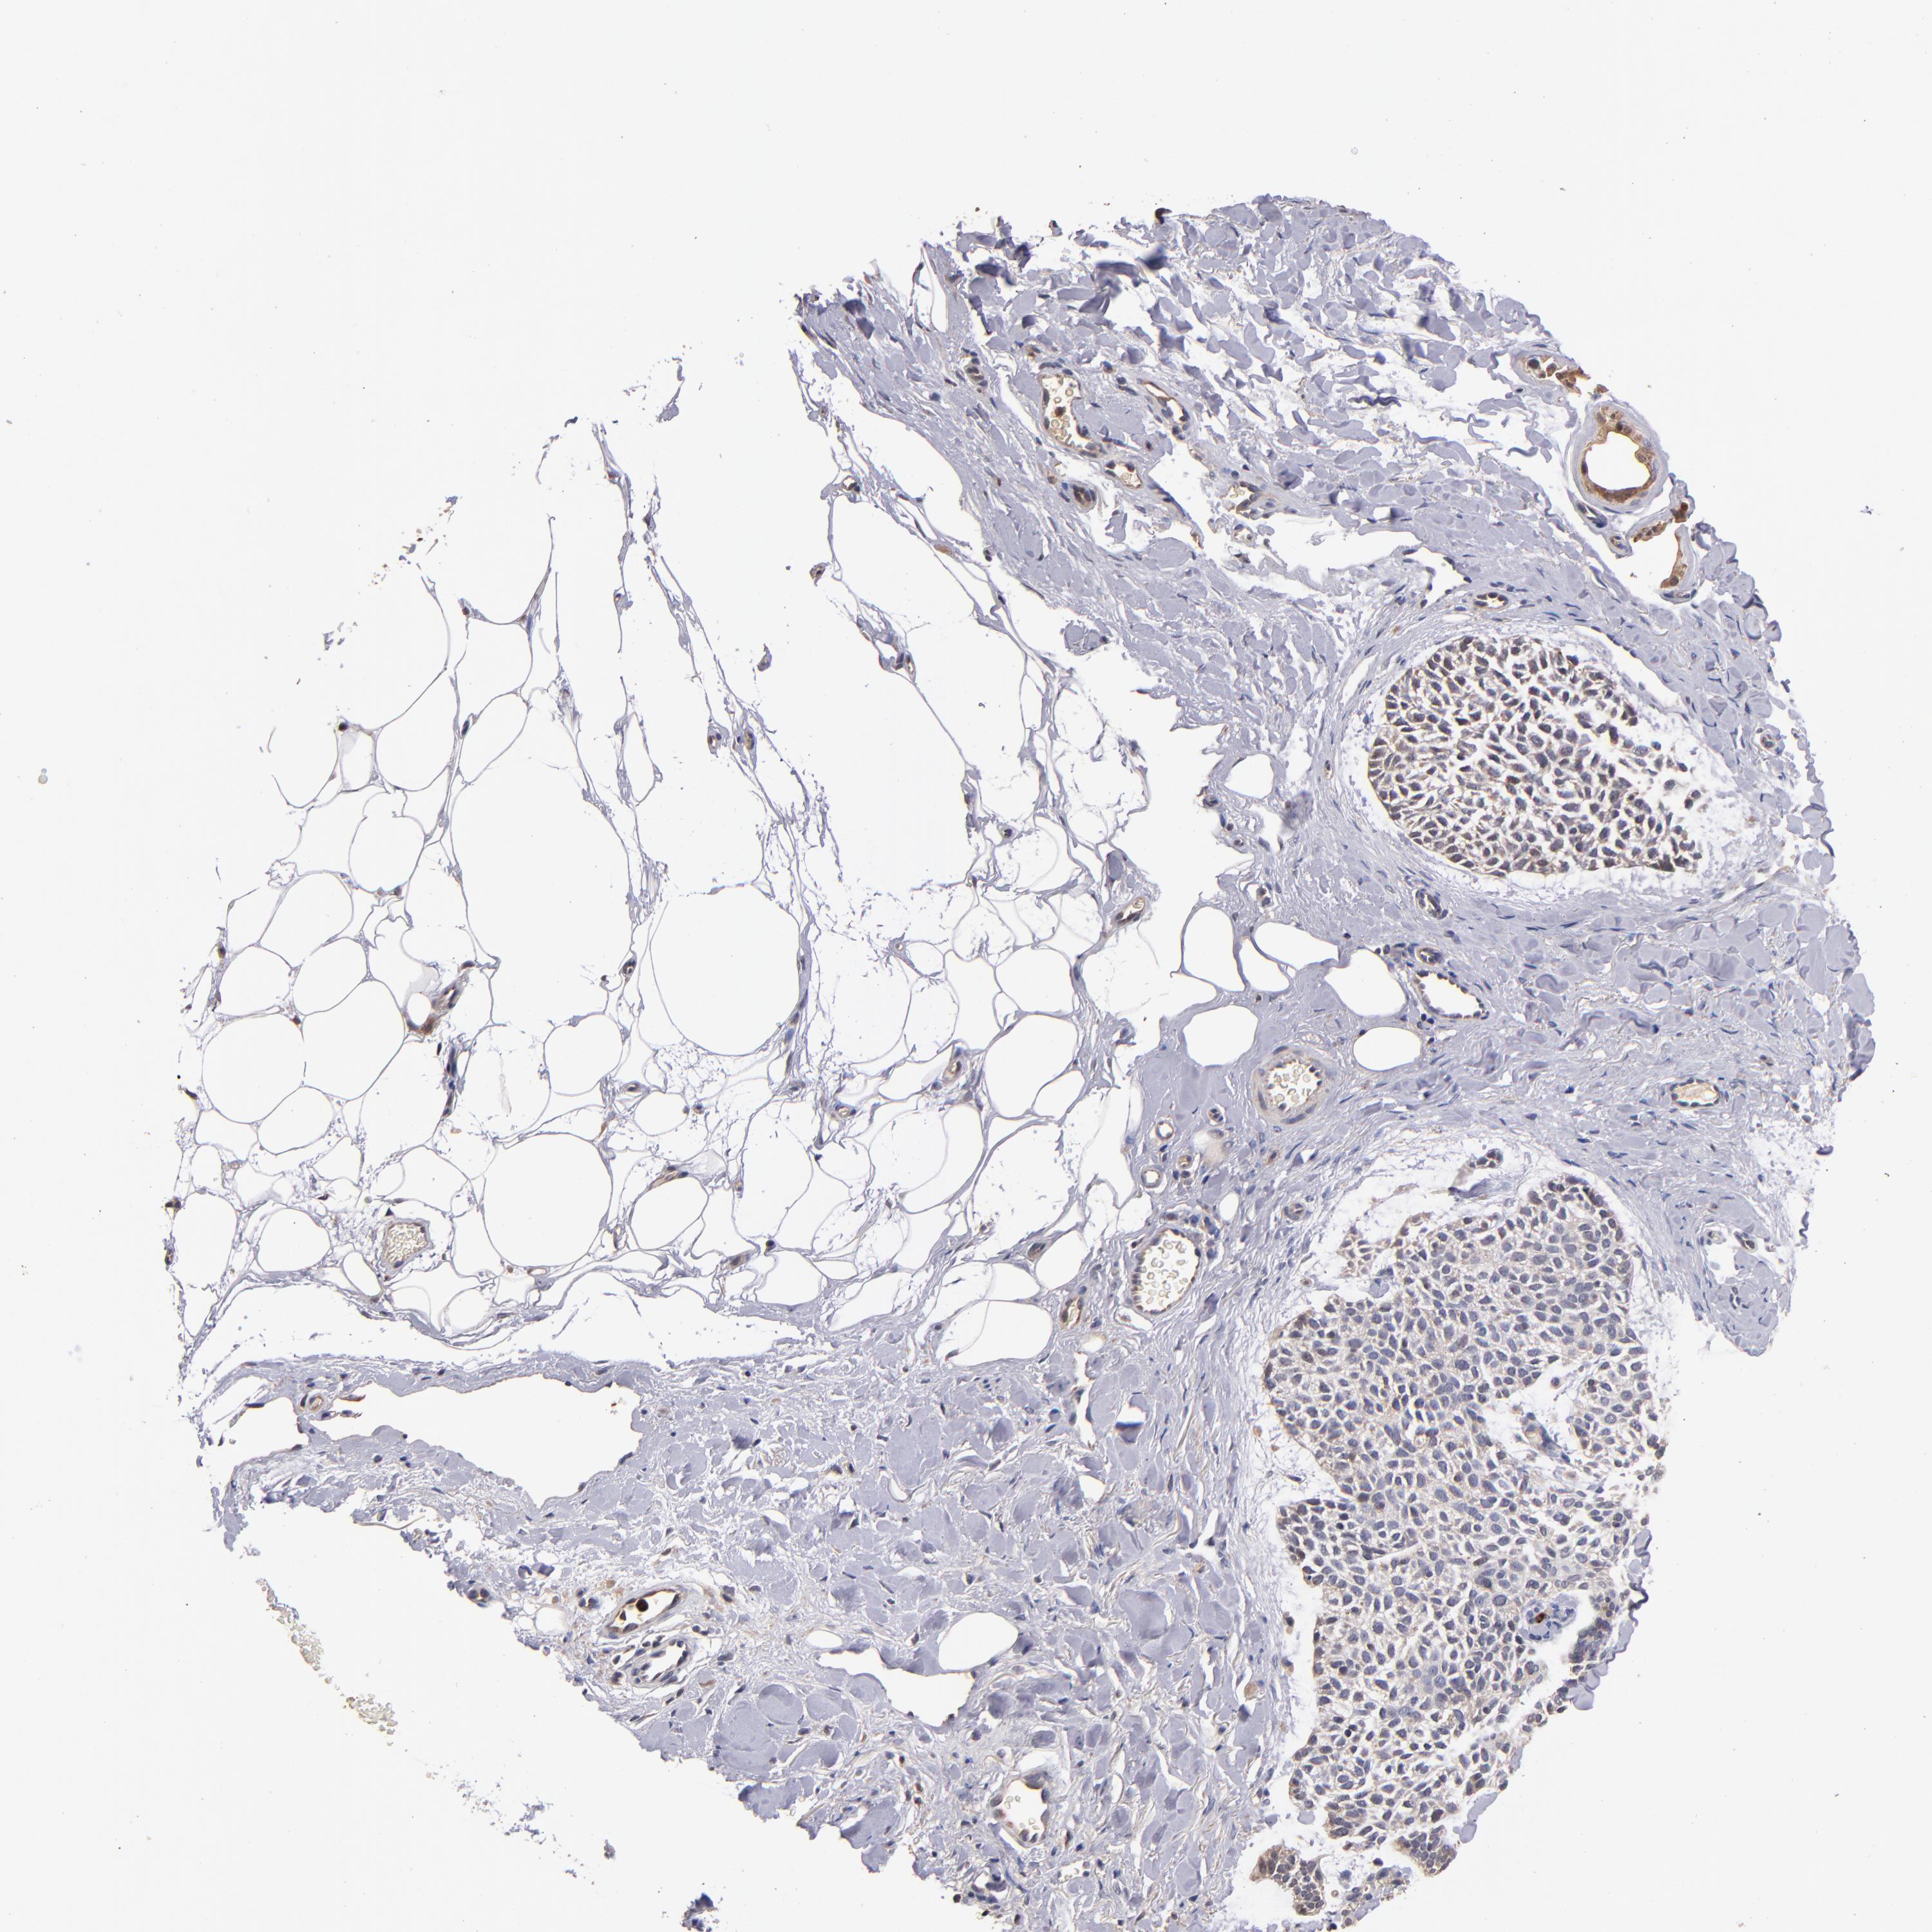

SKIN CANCER - Protein expressioni

A mouse-over function shows sample information and annotation data. Click on an image to view it in a full screen mode. Samples can be filtered based on level of antibody staining by selecting one or several of the following categories: high, medium, low and not detected. The assay and annotation is described here.

Each image is clickable and will lead to virtual microscopy that enables deeper exploration of all samples and also displays staining intensity scores, fraction scores and subcellular localization as well as patient and tissue information for each sample.

Antibody CAB046029

Squamous cell carcinoma, metastatic, NOS